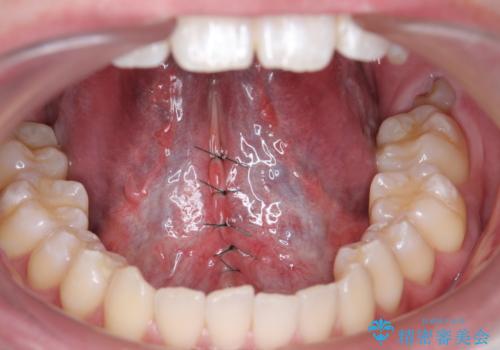

- 舌が動かしにくく、発音に支障があるため、舌小帯切除術を希望された方の症例です。

舌小帯は舌の下にある線維性のスジです。これが短かったり、強直していると、舌運動を上手く行えず、発音や咀嚼・嚥下等に弊害をきたす場合があります。

舌小帯を切除することで舌の可動域が広がり、上記の弊害を改善することが可能です。